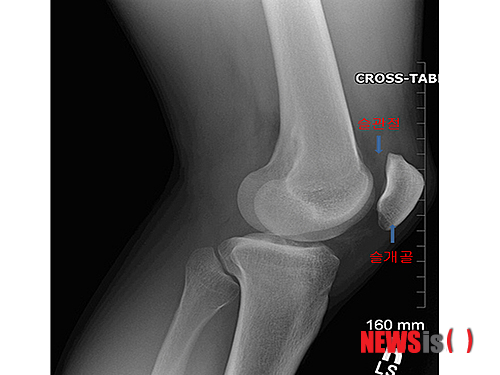

슬개골 연골연화증은 무릎 앞부분 슬개골 뼈가 대퇴골의 뼈와 부딪치면서 연골이 닳는 질환이다. 무릎, 발, 다리의 얼라인먼트에 문제가 생겨 똑바로 움직여야 할 슬개골이 비딱하게 움직이는 것이 원인이다. 무릎, 발, 다리 얼라인먼트의 문제점을 치료하지 않고 줄기세포 연골재생 시술 또는 관절내시경 수술만 하면 일시적으로 통증 완화가 있을 뿐 원인은 치료되지 않는다.